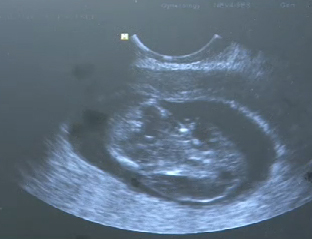

А.Отгонболд /Анагаах ухааны доктор/: Урагт орж халдвар үүсгэж байгаа бактерийн үрэвсэл 100-ны 70% нь байна. Үлдсэн 30% нь вирусны халдвар байна. Энд нэг жишээ дурдвал жирэмсэн эхийн гэдсэнд нь бойжиж байсан хүүхэд нь хоёр толгойтой байгааг бид харж байна. Үндсэн толгойны хажууд дахин нэг толгой ургасан байдалтай байгаа бөгөөд амьдрах чадваргүй гэдэг маань үндсэн толгой нь хоосон тархигүй байх жишээтэй байна.